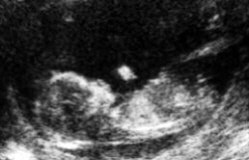

Scanning - Uge 6

Sækkestørrelse = 14 til 25mm CRL (Krone til Hale længden) = 4 til 7 mm Længde = 5,8 til 7,6 mm. / 0,2 til 0,3 inch. |  Nærbillede uge 6 - 3D-scanning. 3D med pile der peger på embryo (CRL). Blommesækken ligger stødende op til embryo. |

Embryo hjerteaktivitet ses med en puls på 126 bpm, 126 HR. |

Fosteret er mellem den hvide markører. En føtalt hjerteslag blev set under denne scanning. |

Den føtale pol vokser med en hastighed på omkring 1 mm om dagen, startende ved den 6. svangerskabsuge. Således er en enkel og nøjagtig måde til at "datere fosteret" tidligt i en graviditet at tilsætte længden af den føtale pol (i mm) til 6 uger. Ved hjælp af denne metode, ville en føtal pol som måler 5 mm have en svangerskabsalder (gestationel) på 6 uger og 5 dage.

Uge 6 - Fosterudvikling ↑Top↑